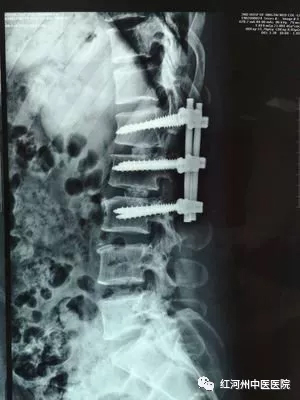

高位腰椎间盘突出症(LDH)

高位腰椎间盘突出症是指L1/2、L2/3、L3/4椎间盘突出,刺激或压迫临近组织而出现一系列的临床症状,它的发病率为5%左右,以L3/4椎间盘突出为主。半数以上的病例为外伤史,既往做过低位腰椎间盘手术的,可能诱发高位腰椎间盘突出。轻的高位腰椎间盘突出可以采取非手术疗法,但对反复发作,出现明显的神经损害表现的应该行手术治疗,手术可以做后路半椎板或全椎板切除术,从硬膜外摘除突出物。

一般可通过病史、体检做出初步判断,但要确诊高位腰间盘突出症,还需要进一步影像学检查,脊髓造影诊断的准确率为80%左右,CT扫描诊断的准确率为90%以上,必要时可以做MRI检查。